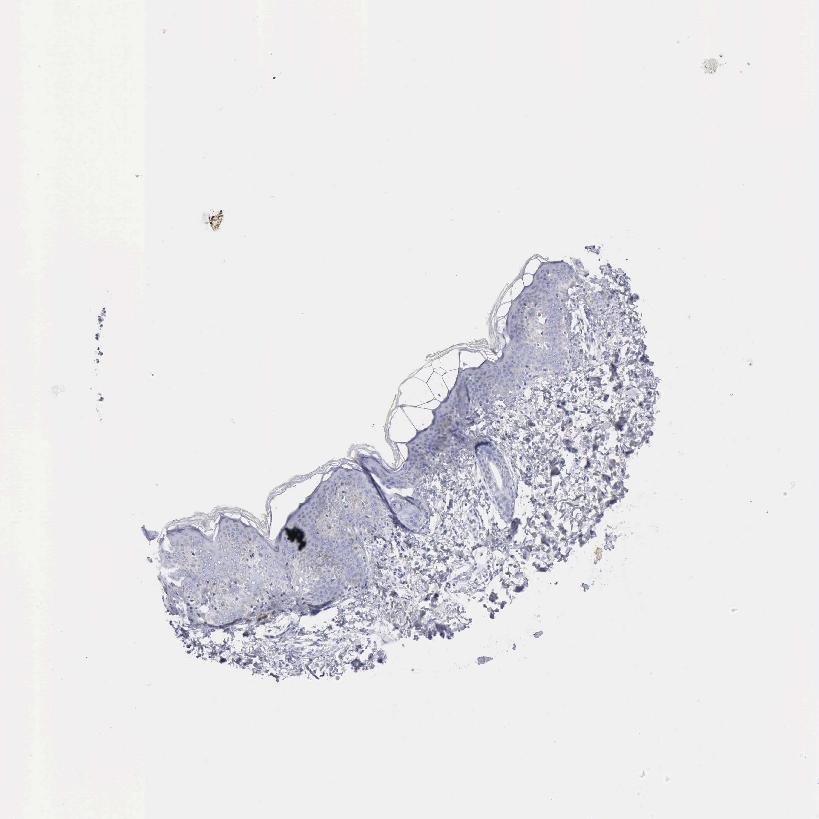

SKIN 1 - Antibody stainingi

Antibody staining in the annotated cell types in the current human tissue is reported as not detected, low, medium, or high, based on conventional immunohistochemistry profiling in selected tissues. This score is based on the combination of the staining intensity and fraction of stained cells.

Each image is clickable and will lead to virtual microscopy that enables deeper exploration of all samples and also displays staining intensity scores, fraction scores and subcellular localization as well as patient and tissue information for each sample.

Antibody HPA003418Antibody CAB000376

Langerhans Not detected-

Cells in basal layer -Not detected

Cells in corneal layer -Not detected

Cells in granular layer -Not detected

Cells in spinous layer -Not detected

Eccrine glands -Not detected

Endothelial cells -Not detected

Extracellular matrix -Not detected

Fibroblasts Not detected-

Fibrohistiocytic cells -Not detected

Keratinocytes Not detected-

Langerhans cells -Not detected

Lymphocytes -Not detected

Melanocytes LowNot detected

Vascular mural cells -Not detected